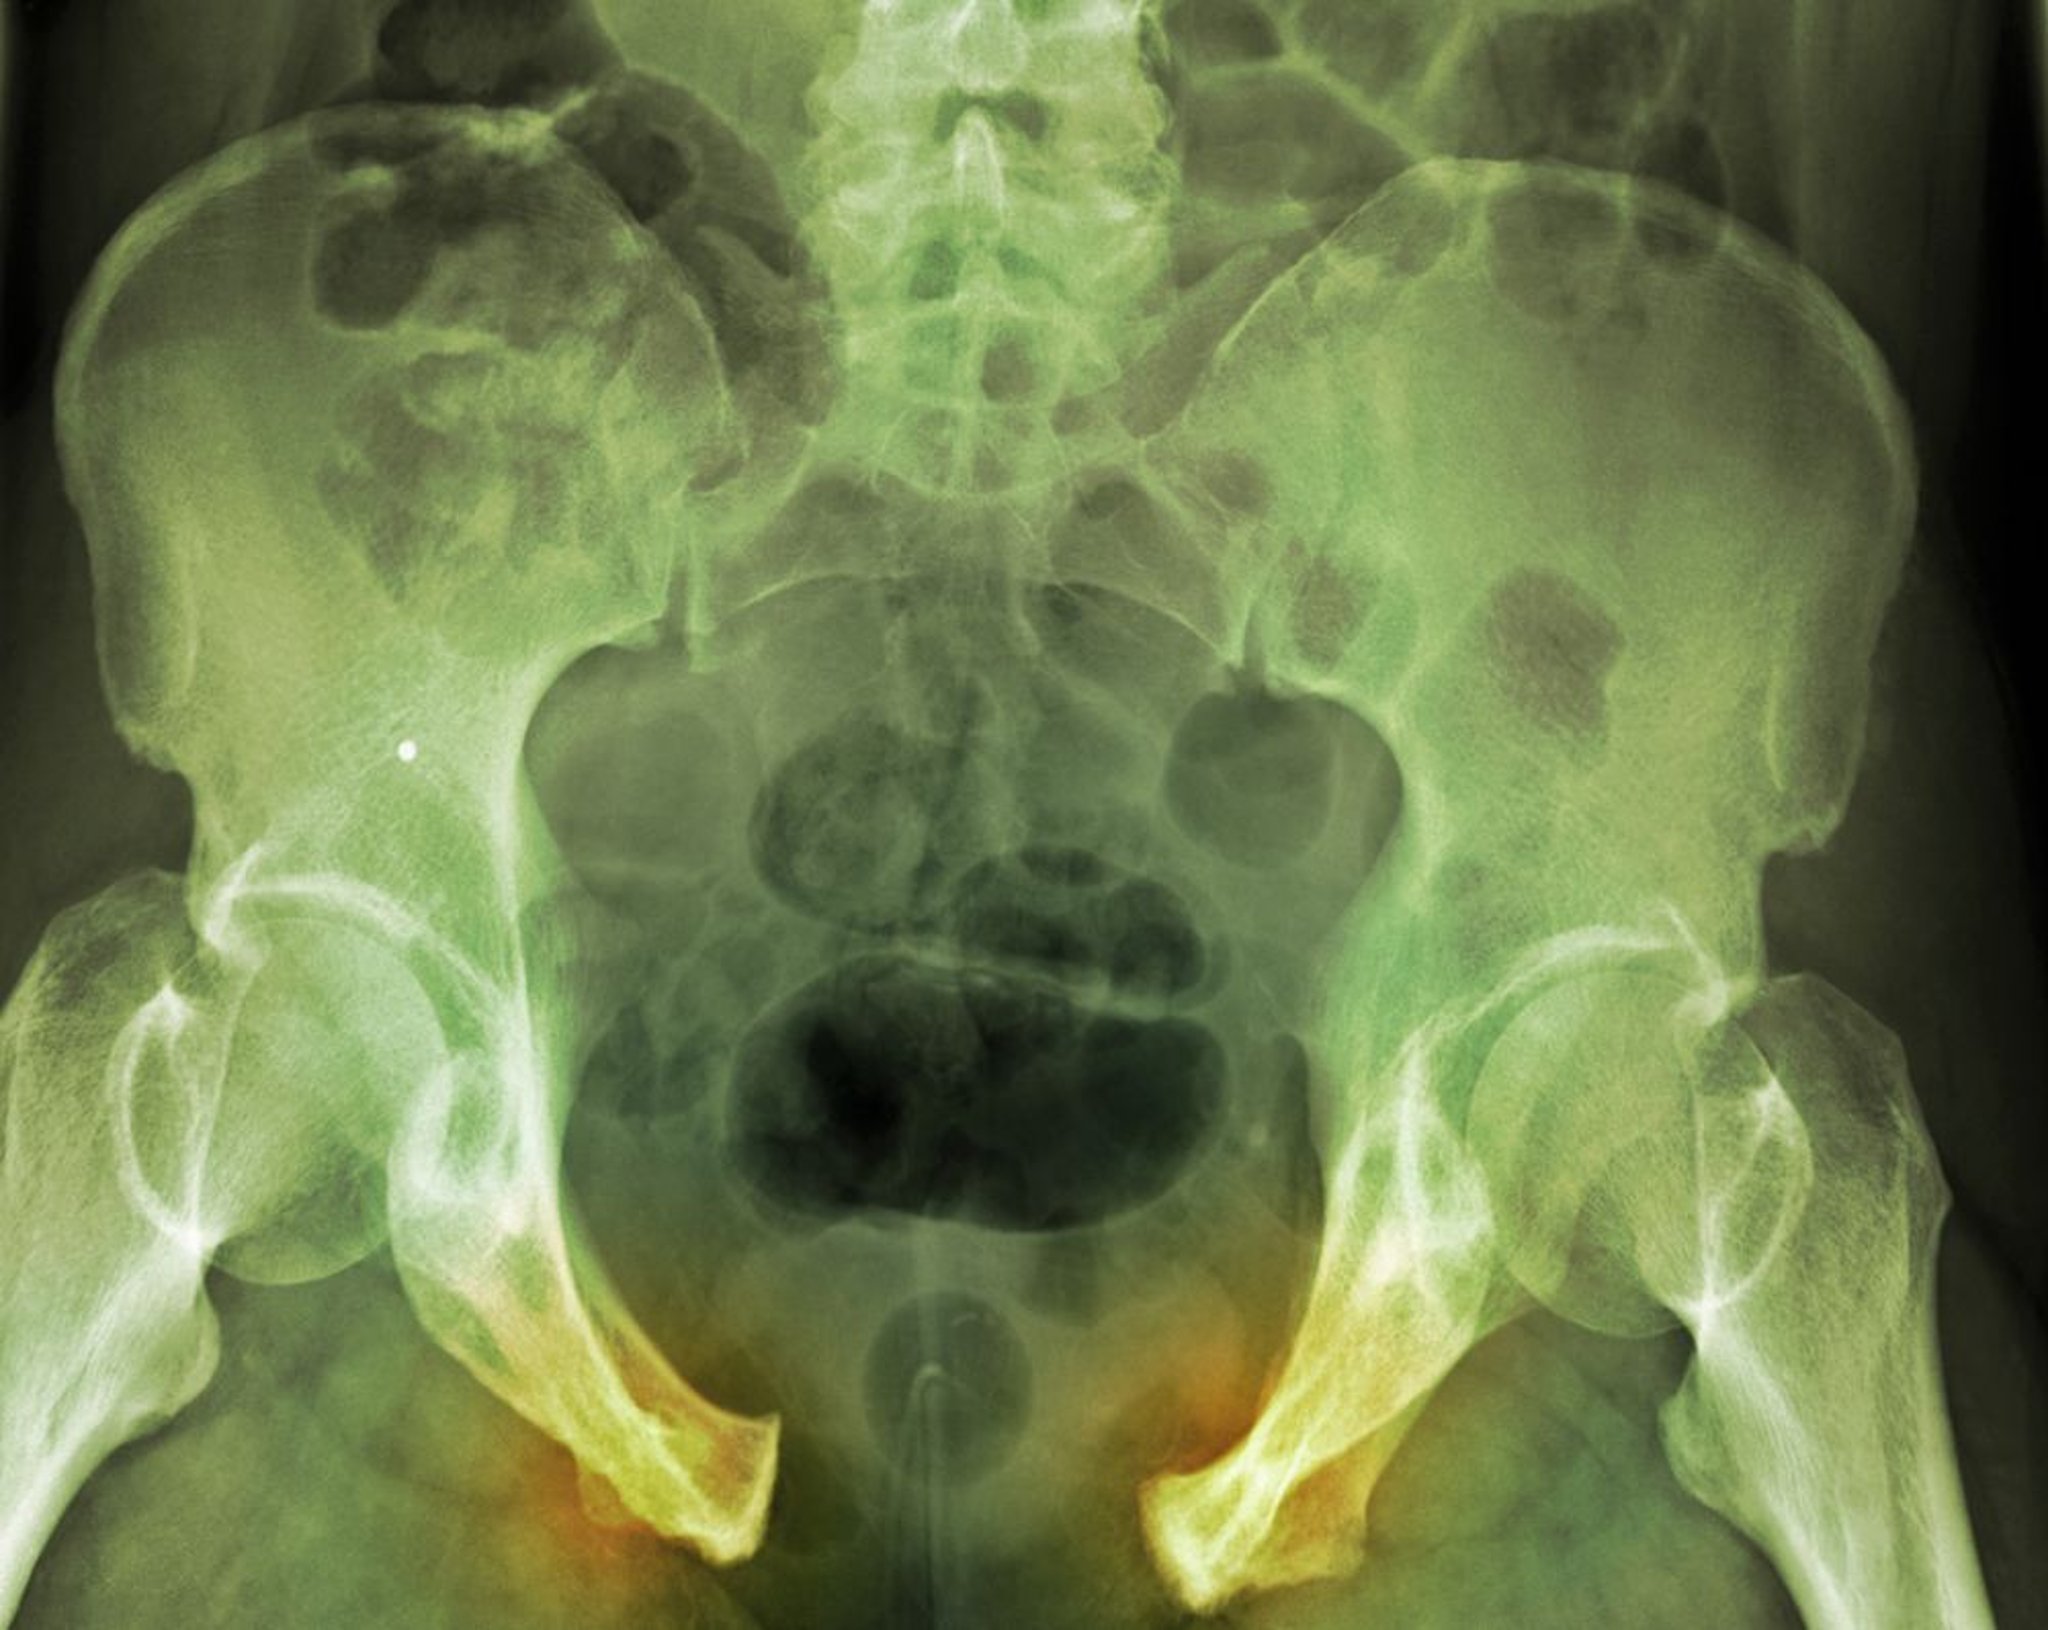

Le fratture pelviche possono coinvolgere la sinfisi pubica, l'osso innominato, l'acetabolo, l'articolazione sacro-iliaca o il sacro. Si va da lesioni stabili minimamente scomposte causate da cadute a bassa energia a lesioni scomposte e instabili drammaticamente dislocate che possono causare emorragie massive. Possono verificarsi anche lesioni genito urinarie, gastrointestinali, neurologiche. La diagnosi viene eseguita tramite RX e spesso tramite TC. Le fratture lievi stabili necessitano solo del trattamento sintomatico. Le fratture instabili e le fratture con importante emorragia di solito richiedono una fissazione esterna o una riduzione aperta con una fissazione interna.

Le fratture pelviche devono essere sospettate se i pazienti hanno dolore nella regione pelvica o all'anca o hanno avuto un grave trauma. Una radiografia in antero-posteriore del bacino mostra la maggior parte delle fratture.

Una frattura scomposta indica che l'anello pelvico è interrotto, suggerendo un'altra frattura o rottura della sindesmosi o legamentosa. Proiezioni radiografiche specifiche (p. es., proiezioni di Judet per visualizzare l'acetabolo) possono essere necessarie.

La TC è più sensibile delle normali radiografie e di solito è fatta per identificare tutti i frammenti di frattura ed alcune lesioni associate quando la frattura è dovuta a un trauma ad alta energia. La TC è spesso inutile quando i pazienti hanno una frattura isolata di un ramo pubico dovuto a un trauma a bassa energia o a una piccola frattura da avulsione.